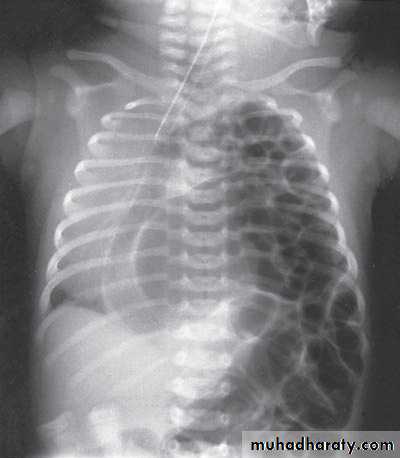

Second photo:

Diagnosis: congenital diaphragmatic hernia

Description: more dextrocardia – diaphragm not present – there is nasogastric tube

severe distress – very tired - 1 day age baby – more number of intestinal loops in

the chest - there is no lung tissue in the chest.

Treatment: pull the intestine ad close the hernia (through abdominal approach).

Scaphoid abdomen